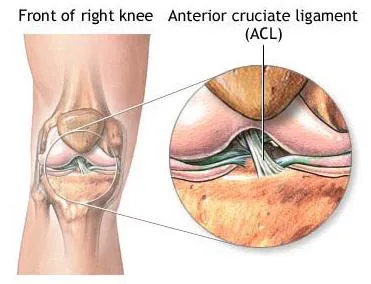

Phương pháp điều trị chấn thương dây chằng

LIỆU PHÁP TIÊN TIẾN TRONG ĐIỀU TRỊ CHẤN THƯƠNG DÂY CHẰNG KHỚP GỐI...

Điều trị chấn thương dây chằng trước tại Bệnh viện Raffles Singapore

Bạn không thể tập thể dục thường xuyên do khớp gối bi lỏng? ...